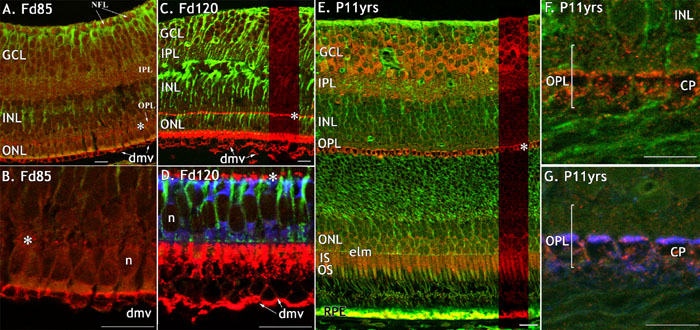

Figure 3. FGFR1 immunoreactivity in monkey fetal and postnatal central retina

FGFR1-IR (red) in fetal and adult macaque retina, double labelled with anti-CRALBP (green; A, B), anti-vimentin (green; C-G) and anti-synaptophsyin (blue; D, G). A: FGFR1-IR is present in axonal bundles in the nerve fiber layer (NFL), on developing pedicles of cone photoreceptors (asterisk) and presumed developing microvilli (dmv) of the retinal pigmented epithelium (RPE). B: FGFR1-IR associated with the developing cone pedicles (asterisk) and on the presumed developing microvilli (dmv). C: Intense FGFR1-IR is present at the level of the developing cone pedicles (asterisk), in the inner segments of cones and associated with in the microvilli (dmv) of the RPE. D: High magnification of the ONL at Fd 120 showing synaptophysin-IR in cones. E: Foveal rim. FGFR1-IR is intense in the GCL and IPL, on cone pedicles (asterisk), inner segments, RPE and to a lesser degree, cone somata. The green labelling in the RPE and at the level of the IS and OS is non-specific. F: A high power view showing FGFR1-IR cone pedicles. G: The same section as F, showing co-localization of FGFR1 protein with synaptophysin on the base of the pedicle. All scale bars represent 20 μm. The cone pedicle (CP), ganglion cell layer (GCL), inner nuclear layer (INL), inner plexiform layer (IPL), inner segment (IS), presumed developing microvilli (dmv), nerve fiber layer (NFL), retinal pigmented epithelium (RPE), ellipsoid (e), external limiting membrane (elm), myoid (m), and nuclei (n) are also identified.